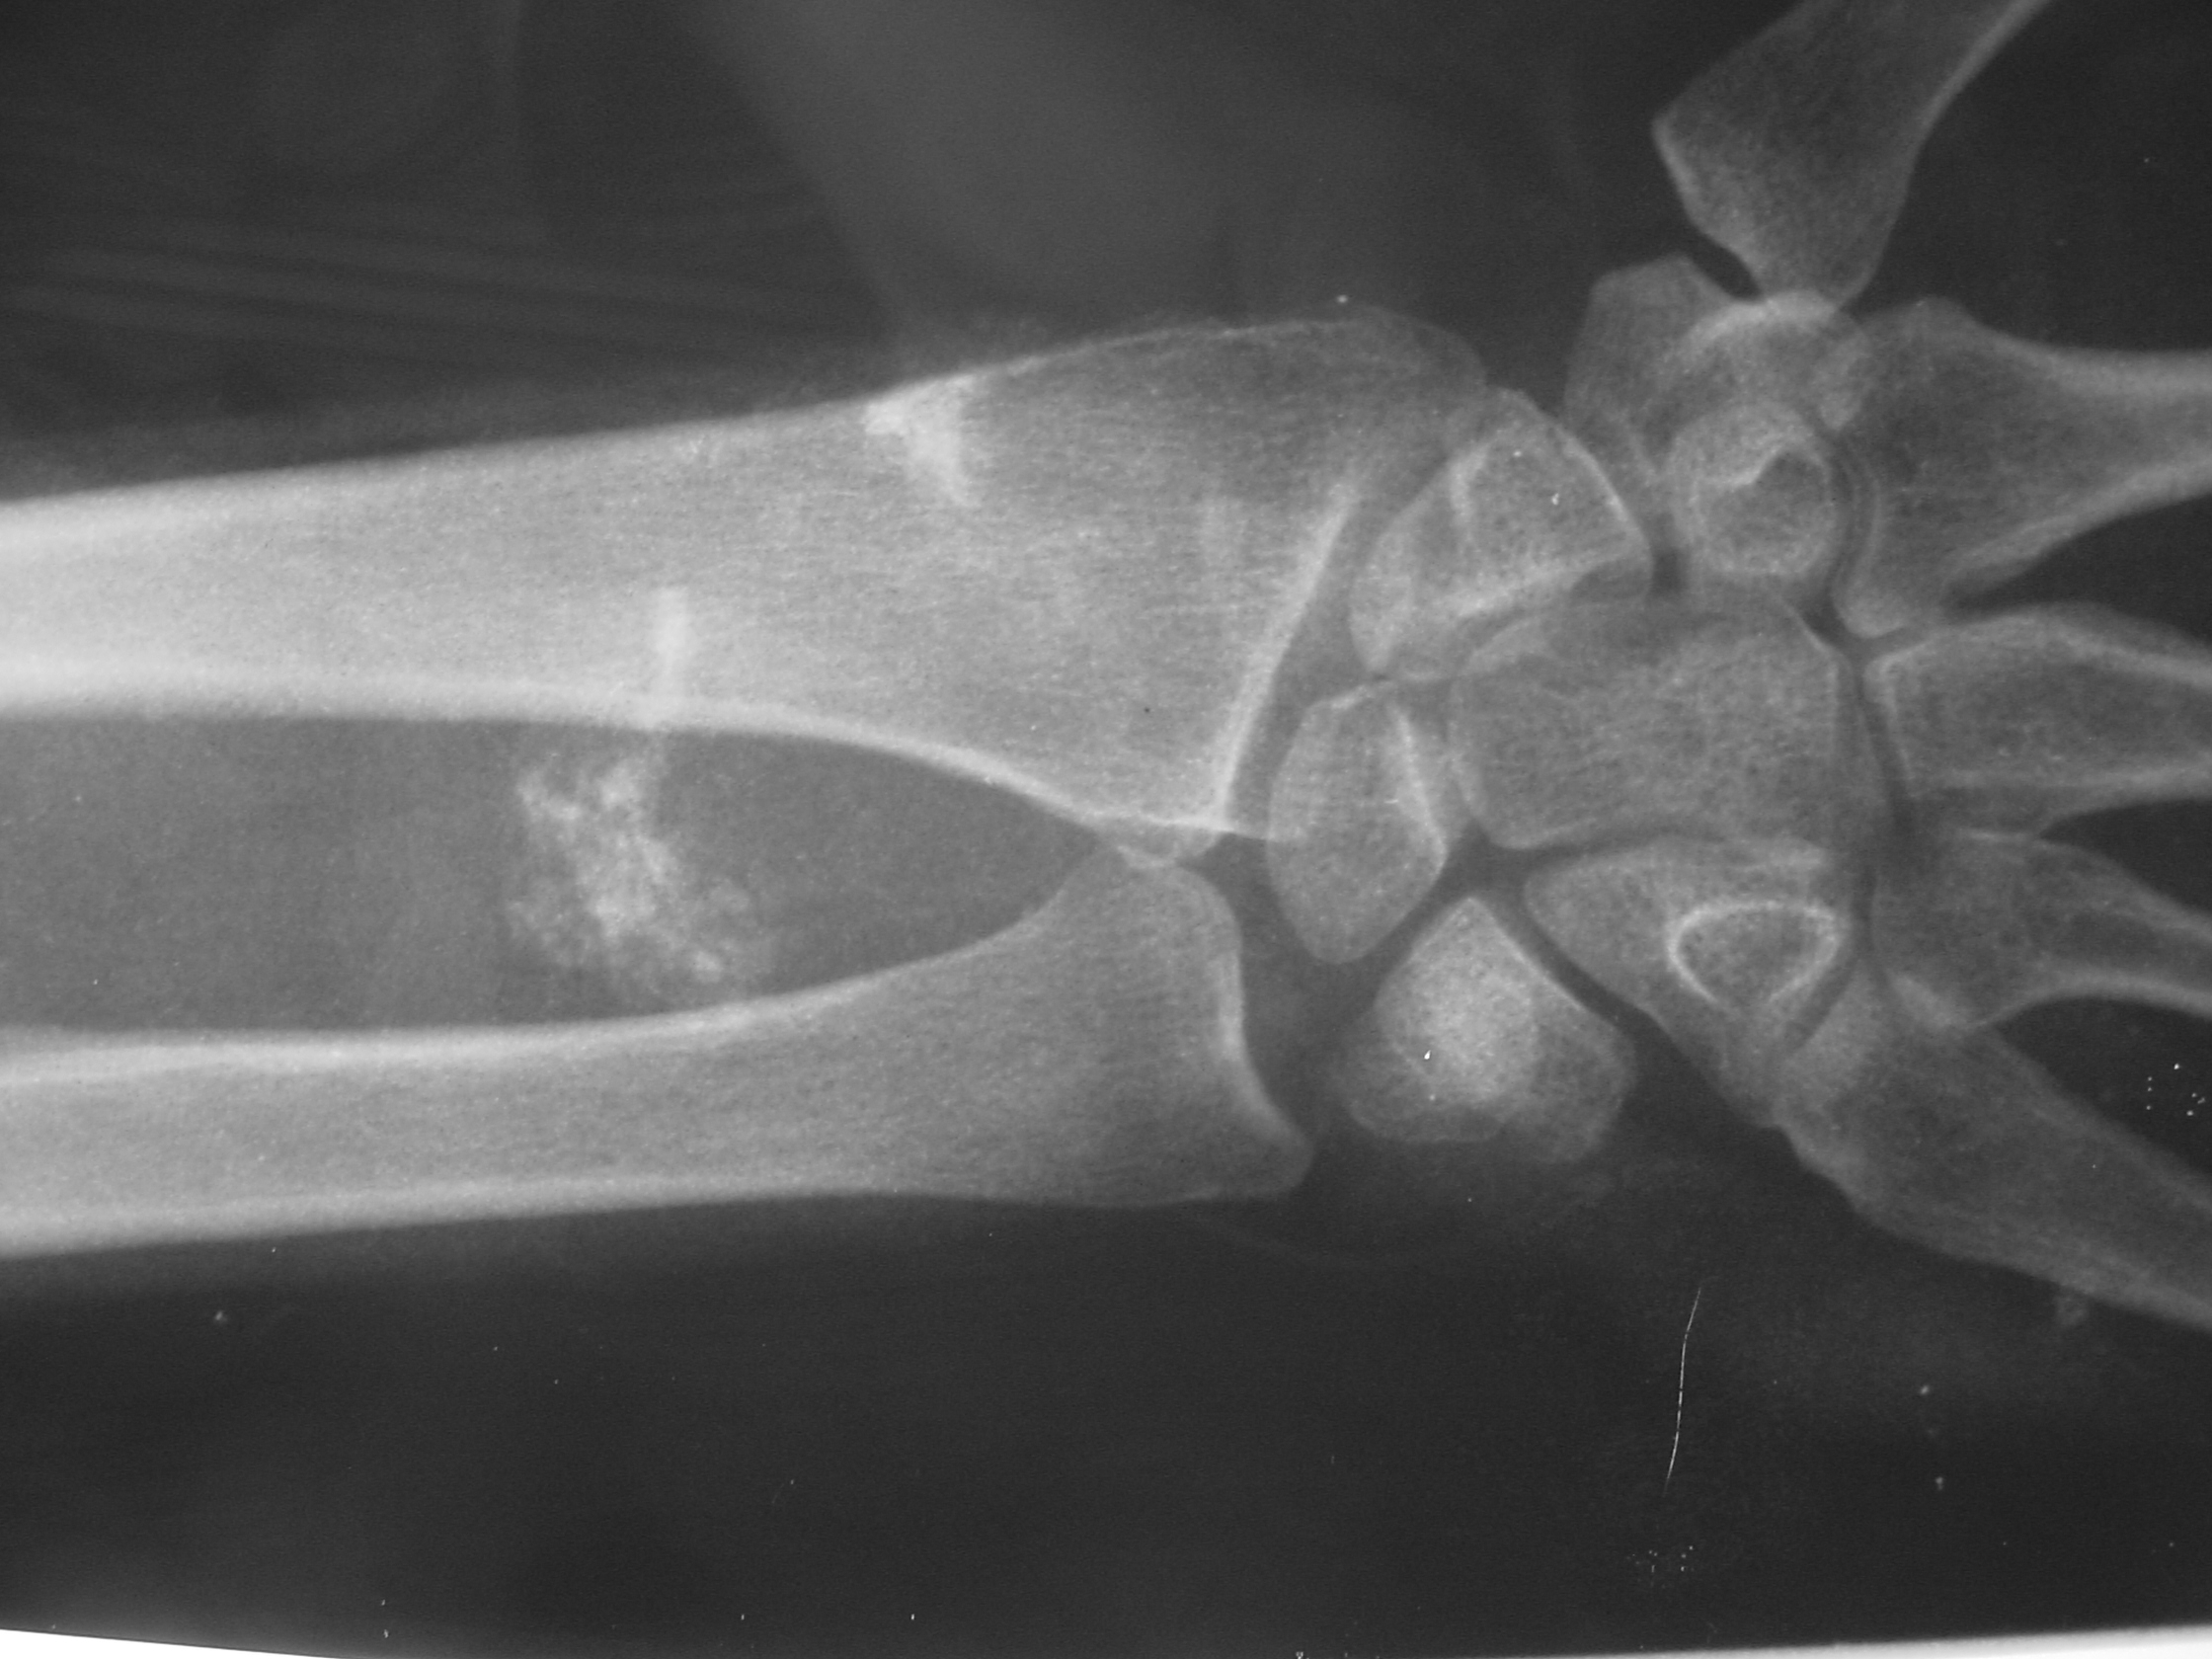

X-rays

Normal in approximately 50% of the cases.

Soft tissue density with mineralization in 30% of cases. This type of mineralization usually presents as calcifications with an irregular contour often in a peripheral distribution.

In 11% to 20% of cases there may be a periosteal reaction, adjacent bony erosion or bone invasion.